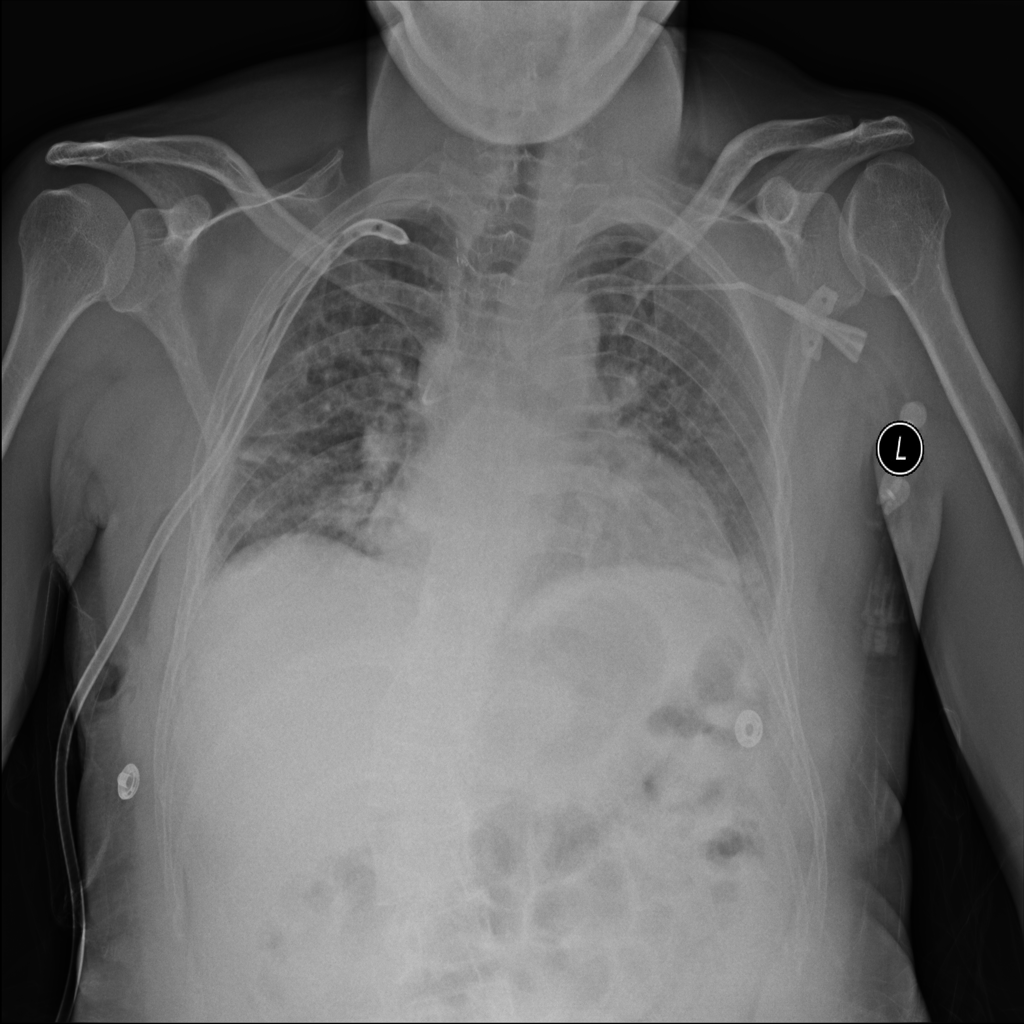

PAT-4639 · IMG-013Pneumothorax

PAT-4639 · IMG-013

AP